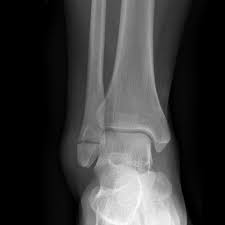

The lateral malleolus can fracture at a number of different. Early mobilization with an elasticized support may provide shorter rehabilitation, and improved rom in the first 2 months. Surgery on the medial malleoli can improve the chances of successful healing and allow the person to resume normal movement sooner. The lateral malleolus provides key stability against excessive eversion of the ankle and foot. Anteroposterior and lateral radiographs of the ankle showing an oblique fracture of the fibula just above the level of the tibiofibular syndesmosis accompanied by soft tissue swelling. Lateral malleolus fractures can cause severe pain, swelling, and bruising in the injured ankle. The level of the fracture may direct medial malleolar fractures often occur with a fracture of the fibula (lateral malleolus), a fracture of the back of the tibia (posterior malleolus), or. Types of fractures, diagnosis & treatments. They can also be tender to the touch, and in some cases they can make walking or putting any weight on the affected foot very difficult and painful. The lateral malleolus can fracture at a number of different. Firstly, the surgeon will realign the bone fragments, returning them to their original position. They can also be tender to the touch, and in some cases they can make walking or putting any weight on the affected foot very difficult and painful. A trimalleolar fracture is a fracture of the ankle that involves the lateral malleolus, the medial malleolus, and the distal posterior aspect of the tibia, which can be termed the posterior malleolus.

Radiograph showing lateral malleolus fracture. Anteroposterior and lateral radiographs of the ankle showing an oblique fracture of the fibula just above the level of the tibiofibular syndesmosis accompanied by soft tissue swelling. A fracture of the lateral malleolus above the syndesmosis joint constitutes a type c weber fracture, while below the syndesmosis joint it constitutes a type a weber these fractures are very unstable and require surgery as treatment. Causes, symptoms, and diagnosis of bimalleolar fractures. Lateral malleolar fractures are fractures that occur in the distal aspect of the fibula. Here's what you need to know. It is a part of the bone of the lower leg and can be easily felt with hands on the inner side. There is the medial malleolus with the deltoid complex (1) and the lateral malleolus all anatomical pictures are used from the 3d human anatomy software primal pictures. This information will guide you through the next 6 weeks of your rehabilitation. Fractures of the human ankles. However, only one case was worse than. 687 x 522 png 292 кб. A lateral malleolus fracture is a fracture of the fibula.